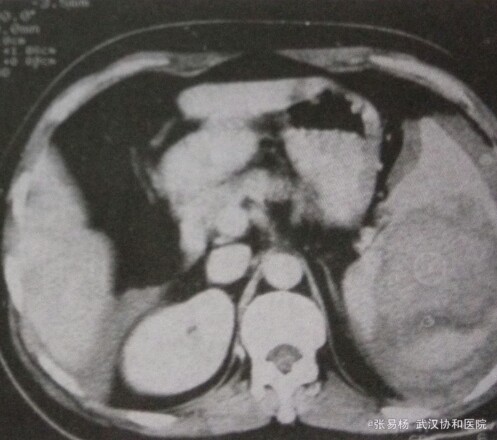

患者,男,65岁 主诉:左侧胸腹部疼痛2天 现病史:两天前从楼梯上摔落,后左侧胸腹部钝痛,今日加剧入院。

体检:胸廓挤压征+,左上腹压痛明显,脾区扣痛明显,无明显反跳痛,急诊腹部穿刺抽出不凝血。 辅检:CT示脾体积增大,脾实质内见结节状、斑片状高低混密度影,增强扫描脾血肿及包膜下积血无强化,脾实质强化。

行脾切除术,手术证实外伤性脾破裂出血、脾内血肿